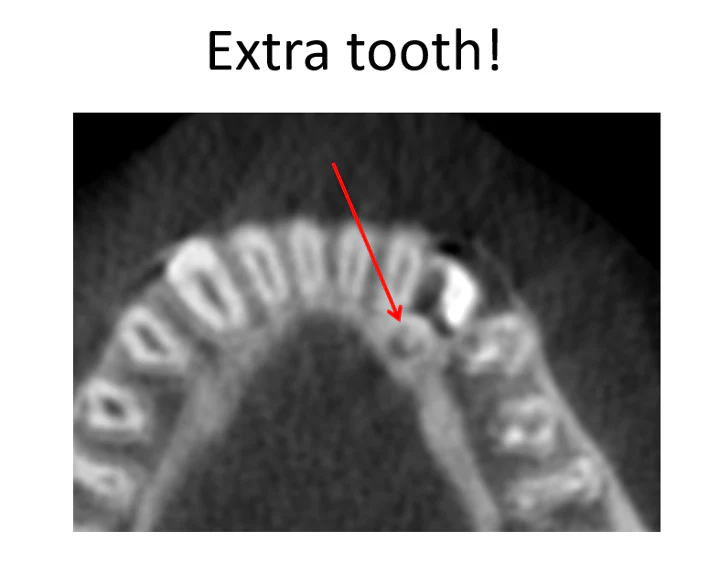

After a cone beam CT scan, the hidden cause became obvious: a very small extra tooth was sitting just behind the impacted canine. That extra tooth was blocking eruption of the adult canine tooth. That finding immediately changed the diagnosis and made it possible to move forward with a treatment plan to help the tooth erupt into a normal position.

In this case, the CBCT dental scan revealed a three-millimeter extra tooth hiding behind the lower canine, wedged near the neighboring incisor. That is exactly the type of detail that can be difficult or impossible to confirm on a standard x-ray alone.

CBCT view identifying the extra tooth that was not visible on the original x-ray.

Figure 2. CBCT view identifying the extra tooth that was not visible on the original x-ray.